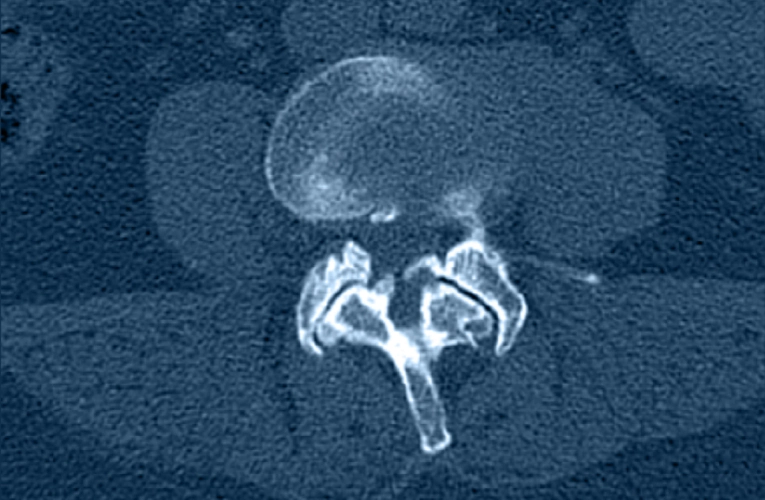

Herniated Disc

What is it?

A herniated disc occurs when the disc’s soft center pushes through a tear in the outer layer and can press on nearby nerves.

How it Happens?

Often from gradual disc degeneration; sometimes triggered by lifting, twisting, or trauma.

Symptoms

Sharp or radiating pain, numbness, tingling, or weakness in the arm or leg—often worse with sitting, coughing, or bending.